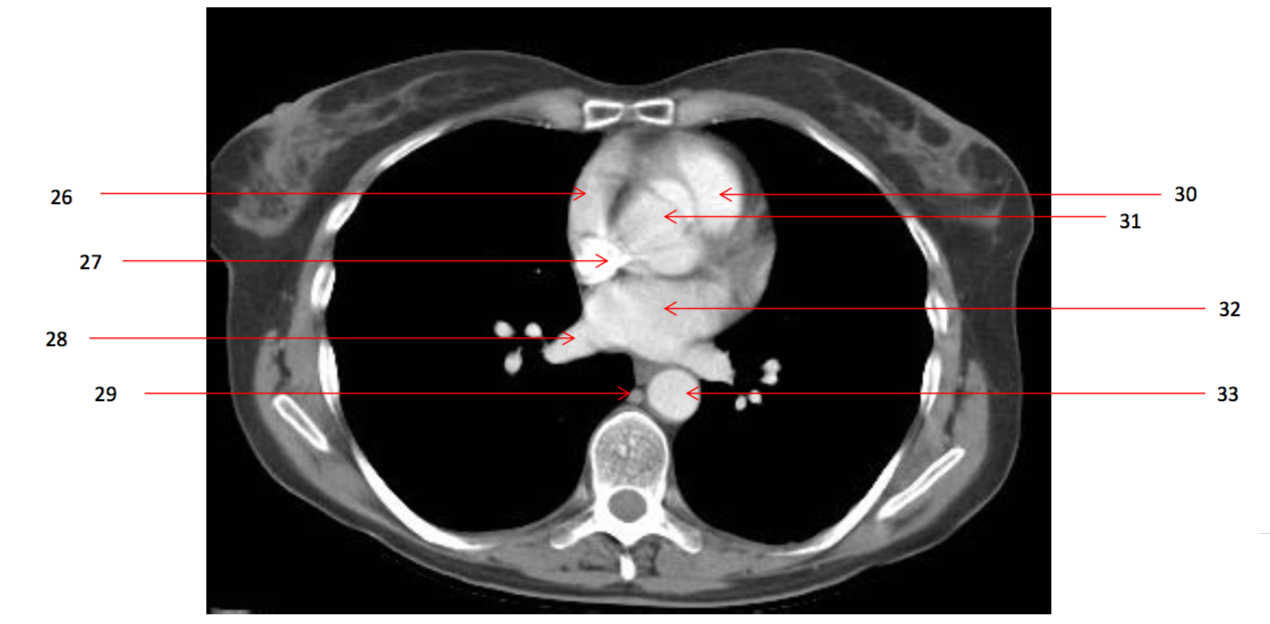

Number 23?

Pulmonary trunk

Number 33?

Descending thoracic aorta

Number 17?

SVC

Number 20?

Ascending aorta

Number 36?

Lt atrium